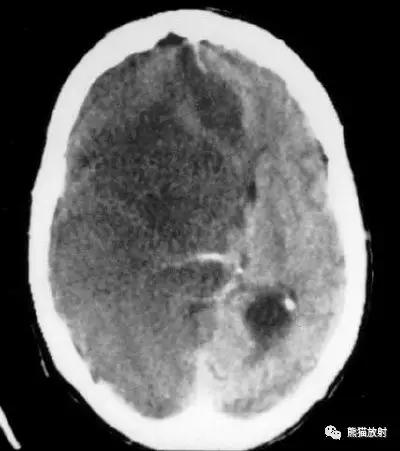

左侧大脑中动脉区完全梗死,对邻近的侧脑室产生占位效应;右侧可见其他较小的缺血性低密度区。